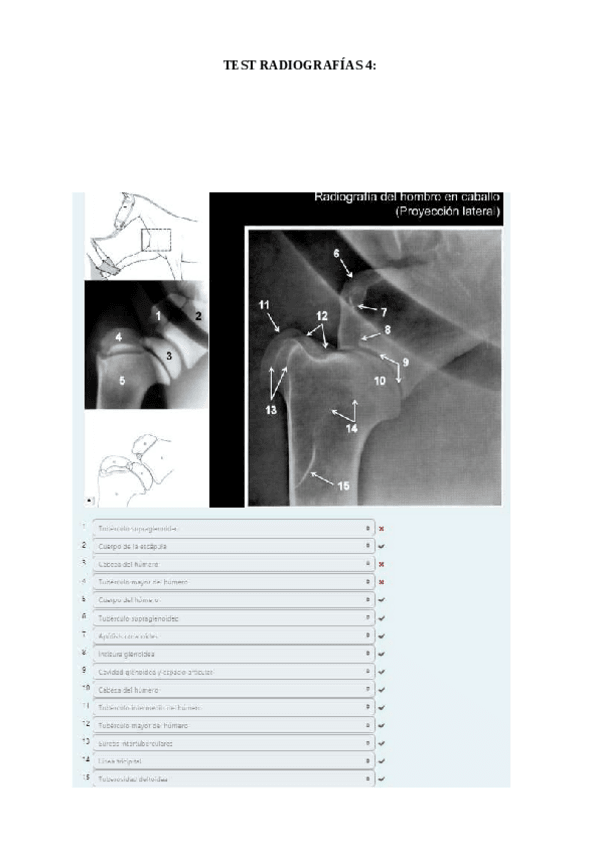

TEST-4-Radiografias-corregido.pdf

Apuntes - Todas-mis-radiografias-resueltas.pdf